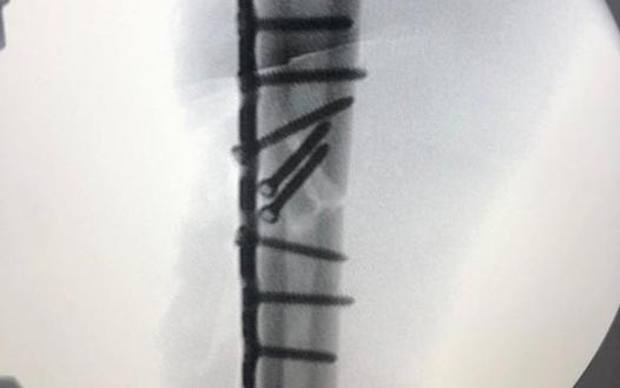

MotoGP, viti e muscoli: ecco il braccio di Marquez dopo l'operazione all'omero

Dodici viti e una placca, giusta la scelta di non scendere in pista per il GP bis a Jerez. Ora la riabilitazione e l'appuntamento di Brno del 9 agosto